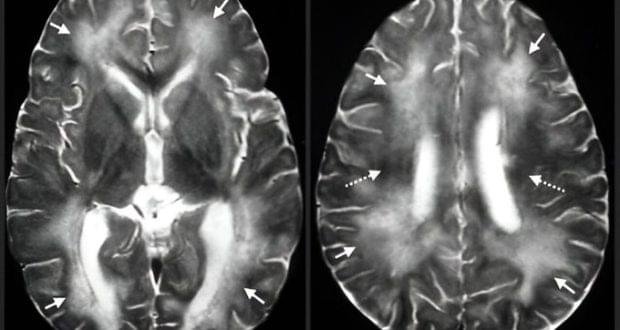

وتحفظت السلطات الصحية الأمريكية عن كشف تطورات الوضع الصحي للمصابين، لكن هذه العدوى غالباً ما تؤدي، في حال انتقالها بين البشر، إلى شلل دماغي، قد ينتهي بالعمى أو الموت.

وبحسب صحيفة إندبندنت، تستغرق الأعراض ما يصل إلى أسبوع لتتطور، بحيث يشعر المصاب بالغثيان، الإرهاق، تضخّم الكبد، فقدان الوعي والتركيز، انعدام السيطرة على العضلات، وصولاً إلى العمى، فالدخول في غيبوبة، ثم الموت.